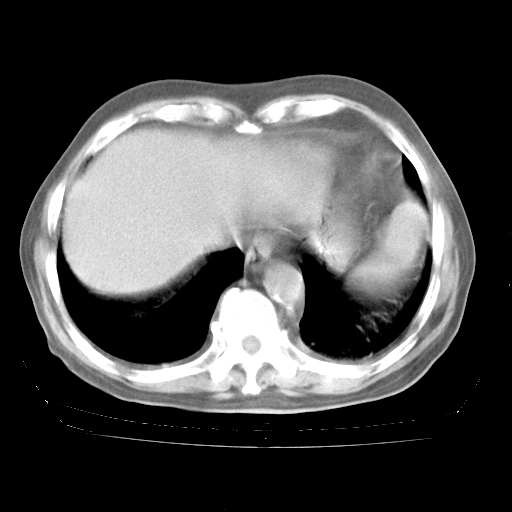

4月28日肺部CT——再次出现类似去年5月9日——透光度降低,“间质性”改变。